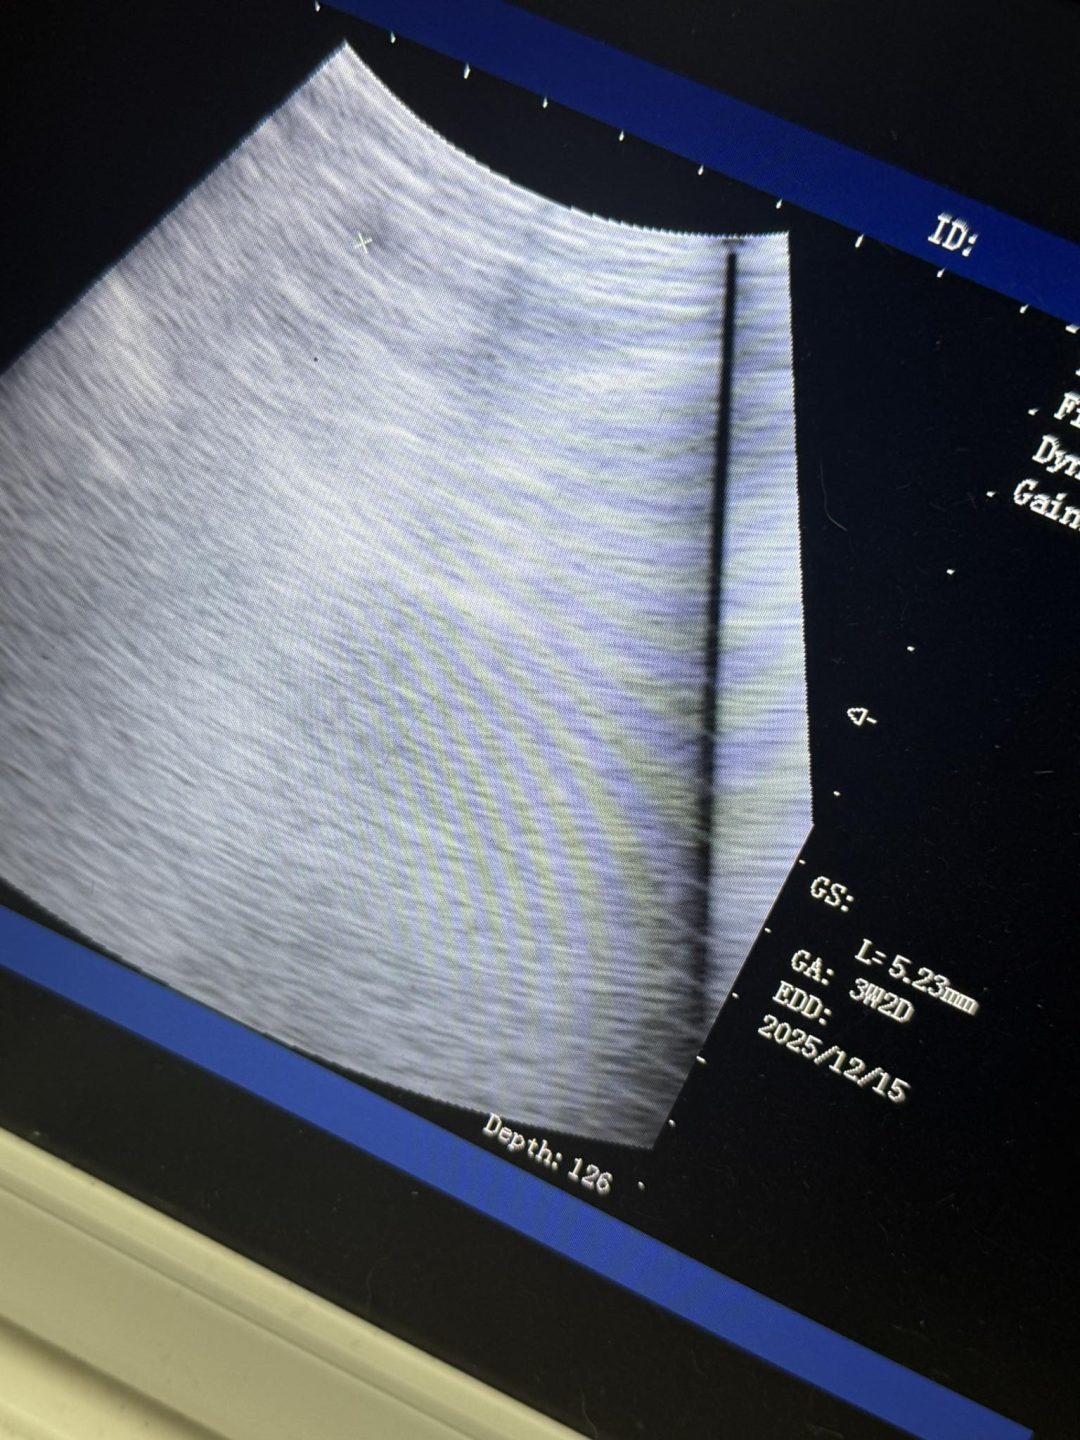

Confirmation ultrasound scan carried out today on a Jack Russell

Unfortunately, the girl was a little early for a scan

I could see the sacs, but could not confirm pups inside the sacs as too small

All the signs are there to say this girl is pregnant, but I have advised her owner to bring her back in around a week to re-scan to see more clearly